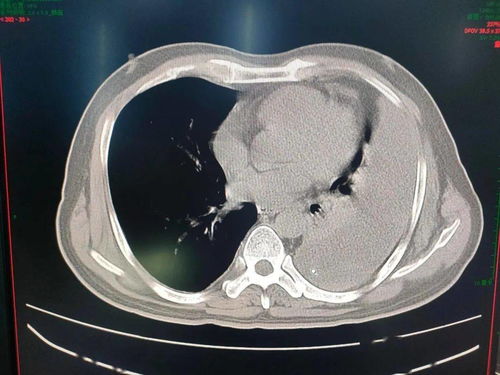

实习期间,我不仅学会了如何诊断与鉴别诊断食管疾病,还参与了多学科协作(MDT)的经验。通过内镜报告和影像学分析,我能区分食管鳞癌、腺癌与良性肿瘤。我观摩了分期手术的决策过程,对手术决策有了更深入的理解。